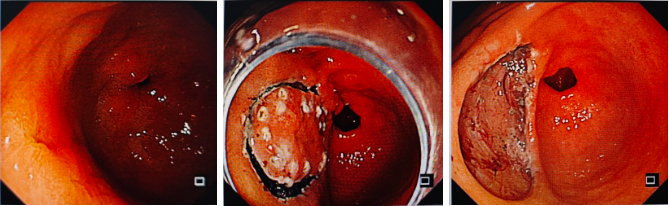

直腸神經(jīng)內分泌腫瘤,ESD完整剝離

直腸神經(jīng)內分泌腫瘤為粘膜下病變,常規(guī)切除會造成病灶切除不盡殘留,ESD治療可完整切除病變。